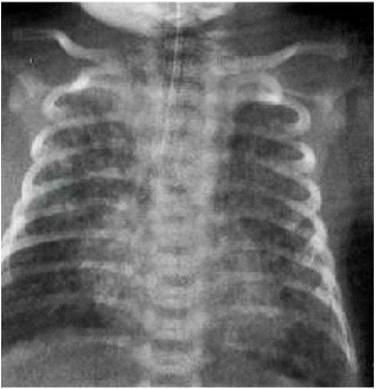

按严重程度可分为三型。轻度:主要表现为肺纹理增粗、斑点斑片状渗出影、肺气肿。中度:主要表现为肺气肿和肺泡渗出,可见颗粒状、片状、团块状、结节状阴影,渗出影密度较高,有些病例见节段性肺不张,以肺气肿为主者,肺透亮度明显增高,心影缩小。重度:两肺颗粒、斑片或团块状影更加广泛,伴严重肺气肿,发生气漏综合征,可见气胸、纵隔气肿(图1)。肺部X线改变常在7~10天逐渐好转,但有时会持续数周。

图1 胎粪吸入综合征胸片表现

肺纹理增多增粗,两肺过度膨胀,膈面压低,可见斑片状渗出影与过度膨胀区间隔现象。